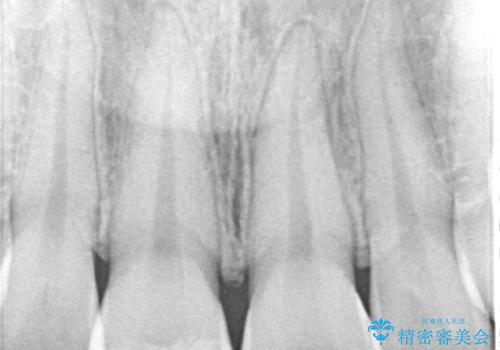

- 前歯が欠けてしまい、保険診療の樹脂の材料で修復していた前歯をきれいにしたいと来院された患者様です。

歯の約半分が欠けてしまっているため、樹脂の材料での修復には限界があります。

土台の形を整えて、精度の高いシリコーンによる型どりを行いました。